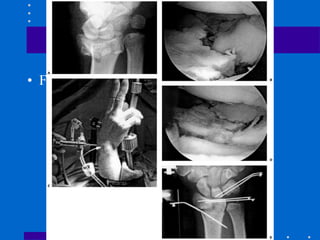

Fixação Externa

+ Redução aberta e fixação

interna

• Cominuição dorsal e volar de alta energia,

fragmentos não permitindo fixação interna

somente

• Varias coortes com sucesso

• Evita abordagem dupla dorsal e volar

• Figura 26-22